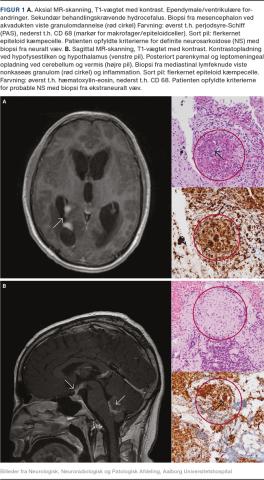

Meninges

Diffus inflammation og noduli i leptomeninges er en hyppigt set tilstand og viser sig klinisk som subakut lymfocytær meningitis med hovedpine og rammer især de basale meninges [4-6], men kan være placeret over konveksiteterne. Komplikationer er ventrikulitis, hydrocefalus, evt. med livstruende forhøjet intrakranielt tryk (Figur 1A) eller kranienerveudfald.

Hjerneparenkym

Sarkoid inflammation og granulomer i hjernen kan give en række neurologiske problemer afhængigt af udviklingshastighed, lokalisation og omfanget af den inflammatoriske proces. Ved NS ses der ofte påvirkning af hypofysen og hypothalamus [7, 9-11] (Figur 1B), hvilket kan give neuroendokrine forstyrrelser som hypofyseinsufficens og chiasmainvolvering med synsudfald eller hypotalamiske symptomer med træthed, tørst, apati og ændret temperaturregulering. NS i andre dele af hjernen kan bl.a. give epileptiske anfald, hemiparese, afasi eller ataksi afhængigt af inflammationens placering [5, 7, 9]. Spredte periventrikulære og subkortikale white matter lesions (WM-læsioner), som giver mere diffuse symptomer, ses. Vaskulære forandringer, som er udløst af vaskulitis, eller inflammatorisk tryk på arterier eller hjernens drænvener, kan give et strokelignende billede [12].

Ved NS anvendes MR-skanning med gadoliumkontrast [10, 16]. Inflammation ses som øget kontrastoptagelse bedst på T1-vægtede sekvenser (Figur 1og Figur 2). MR-skanningsfund, der rejser særlig mistanke om NS er: inflammatoriske forandringer ved kranienerver, i leptomeninges, i hjernevævet især omkring hypofysen/hypothalamus eller tumorlignende granulomer (Figur 2A), evt. med masseeffekt. Diffus og/eller nodulær leptomeningeal opladning er typisk, især i basale meninges og kan give involvering af kranienerver eller hydrocefalus. Periventrikulære eller subkortikale WM-læsioner er hyppige. I medulla er leptomeningeal opladning og/eller granulomer, oftest lokaliseret torakalt evt. som en langstrakt læsion over 2-3 segmenter typisk [13].